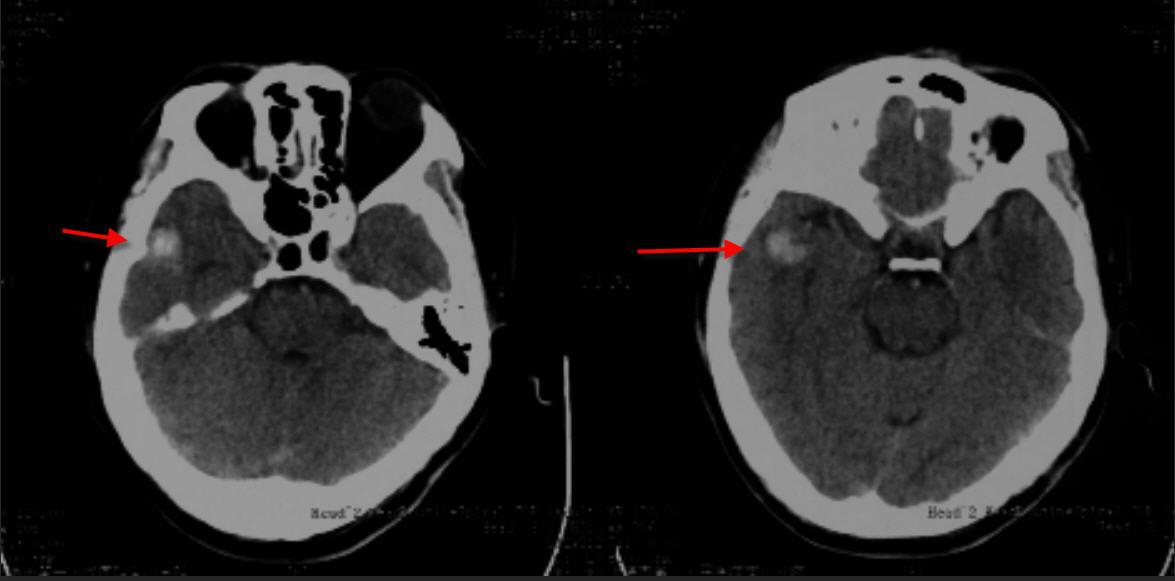

2019年2月25日头颅平扫+图像重组CT片示:左额部头皮软组织肿胀,右侧颞叶见类圆形高密度影,中线结构居中。

2019年2月26日头颅平扫+图像重组CT片示:左额部头皮软组织肿胀较前恢复,右侧颞叶见类圆形高密度影,较前无动态变化。

2019年3月14日头颅平扫+图像重组CT片示:左额部头皮软组织肿胀已恢复,右侧颞叶见类圆形高密度影,较前无动态变化。

现本院审阅许某受伤当天影像学资料显示左额部头皮软组织肿胀,右侧颞叶见类圆形高密度影,中线结构居中;伤后3周复查头颅CT显示左额部头皮软组织肿胀已恢复,右侧颞叶见类圆形高密度影,较前无动态变化;伤后1月余复查头颅MRI显示右侧颞叶见类圆形异常信号影,呈T1高信号,FLAIR周边高、中央低信号,随访无动态变化;近期本院复查头颅CT显示右侧颞叶见类圆形高密度影,较前无动态变化。综上,分析其右侧颞叶类圆形高密度影,形态、密度等随时间变化无动态改变,不符合外伤后脑出血灶的演变规律,考虑系自身占位性病变(右侧颞叶海绵状血管瘤),与本次头部外伤之间存在因果关系的依据不足。

受伤当天头颅CT片显示右侧颞叶见类圆形高密度影

受伤当日头颅CT片显示右侧颞叶见类圆形高密度影 4月12日头颅CT片未呈现动态变化